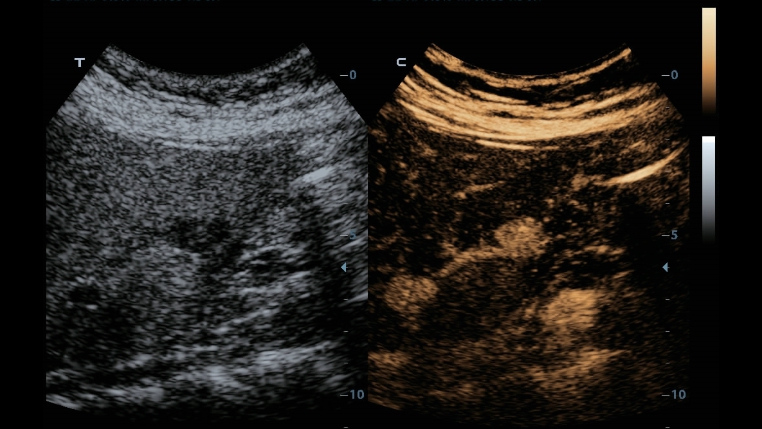

Klasik g?rÞntÞleme teknolojileri: Tan? i?in kalitenin artt?r?lmas?

Yerle?ik ultrason sistemlerinden aktar?lan klasik g?rÞntÞleme teknolojilerinin uygulanmas?yla, Full HD ?zellikli DC-40, g?rÞntÞ ayr?nt?lar?nda size kalite art??? sunar.

- ?Clear (benek azaltma g?rÞntÞleme teknolojisi)

- PSH (Faz Kayd?rma Harmonik g?rÞntÞleme)

- ?Beam: mekansal bile?ik g?rÞntÞleme teknolojisi